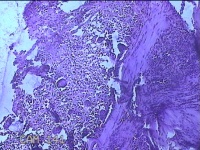

右侧中指尺侧包块

性别

女

年龄

53岁

临床诊断

肌腱腱鞘囊肿

一般病史

发现右侧中指尺侧一包块1年余,无明显疼痛及不适。

标本名称

大体所见

灰白暗红色肿物1.2x0.8x0.3cm一个,表面糜烂,切面灰白粉红色,质软。